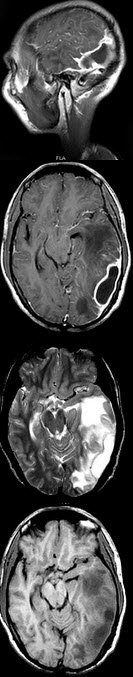

患者,男,70岁,有高血压病史8年,有房颤病史15年,突起右侧肢体无力6小时入院。体查:心率110次/分,率不齐,血压170/100mmHg,神志清楚,双眼左侧凝视,右侧鼻唇沟浅,伸舌偏右,右侧肌力2级。脑MRI见如图所示病灶。 该病灶为哪根血管支配( )

A:大脑中动脉

B:颈内动脉

C:大脑后动脉

D:椎—基底动脉

E:大脑前动脉